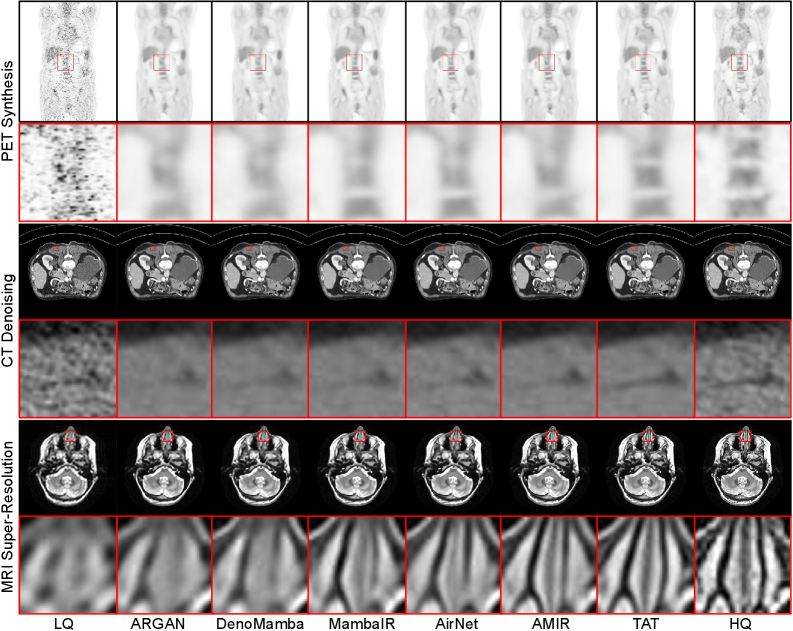

Refer to caption

Figure 2: Visual comparisons on All-in-One medical image restoration.

All-in-One Medical Image Restoration. The results of All-in-One MedIR are presented in Table. 2, where TAT significantly (p<0.05p<0.05) outperforms all comparison methods across all three tasks. Especially, it outperforms AMIR which is the current SOTA method in All-in-One MedIR. This is because TAT best deals with the inter-task relationships of task interference and task imbalance. In fact, our proposed TAT even achieves a comparable performance to task-specific models present in Table. 1. This indicates that TAT has strong model capacity and adaptability to deal with diverse tasks. The visual comparisons in Fig. 2 further highlight TAT’s superior ability to consistently restore finer structures and details of images across different tasks.